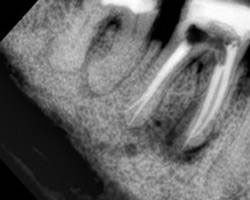

На этом рентгеновском снимке видны, в первую очередь, «пустые» корневые каналы и довольно больших размеров очаг воспаления (то, что часто называют гранулемой, кистой) на верхушке одного из корней. В общем итоге в одном зубе был сконцентрирован целый букет ошибок и недоделок, одним словом, это образец недобросовестной работы стоматолога. Я стараюсь о коллегах всегда говорить или хорошо или молчать, но в данном случае надо смотреть правде в глаза – зуб загублен именно стоматологом. Никаких объективных сложностей для качественной работы изначально здесь не было. Зато появились теперь. Прогноз на будущее для таких зубов всегда строится, исходя из 2 основных проблем – насколько приведет к успеху повторное лечение каналов и насколько будет успешной попытка адекватного восстановления зуба после этого. Оценив вероятность долговременного успеха этих двух составляющих, можно решать, стоит ли «спасать» зуб от щипцов хирурга. Ведь, в любом случае, лечение стоит денег, а гарантировать результат здесь невозможно. Можно только предполагать вероятность успеха. В данном случае каналы не выглядели непроходимыми. Да и восстановить зуб коронкой, даже несмотря на большую степень разрушения, все еще представлялось возможным. А потому было принято решение о начале лечения.